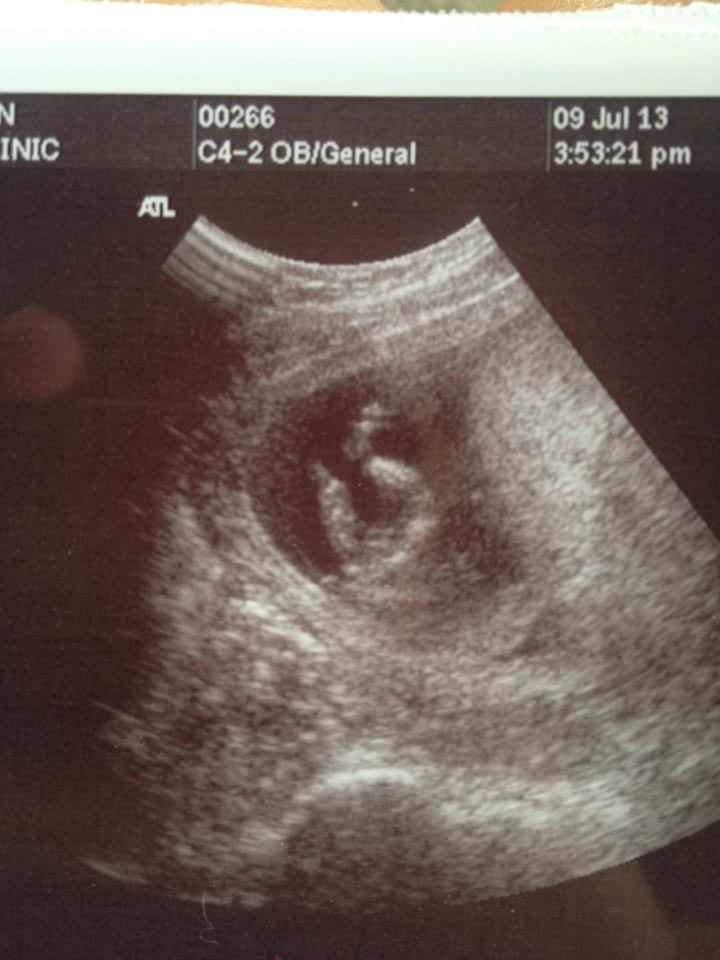

Attachment 12723 Boy or girl at 13 weeks??

Does anyone have a reply to whether this may be a boy or girl??